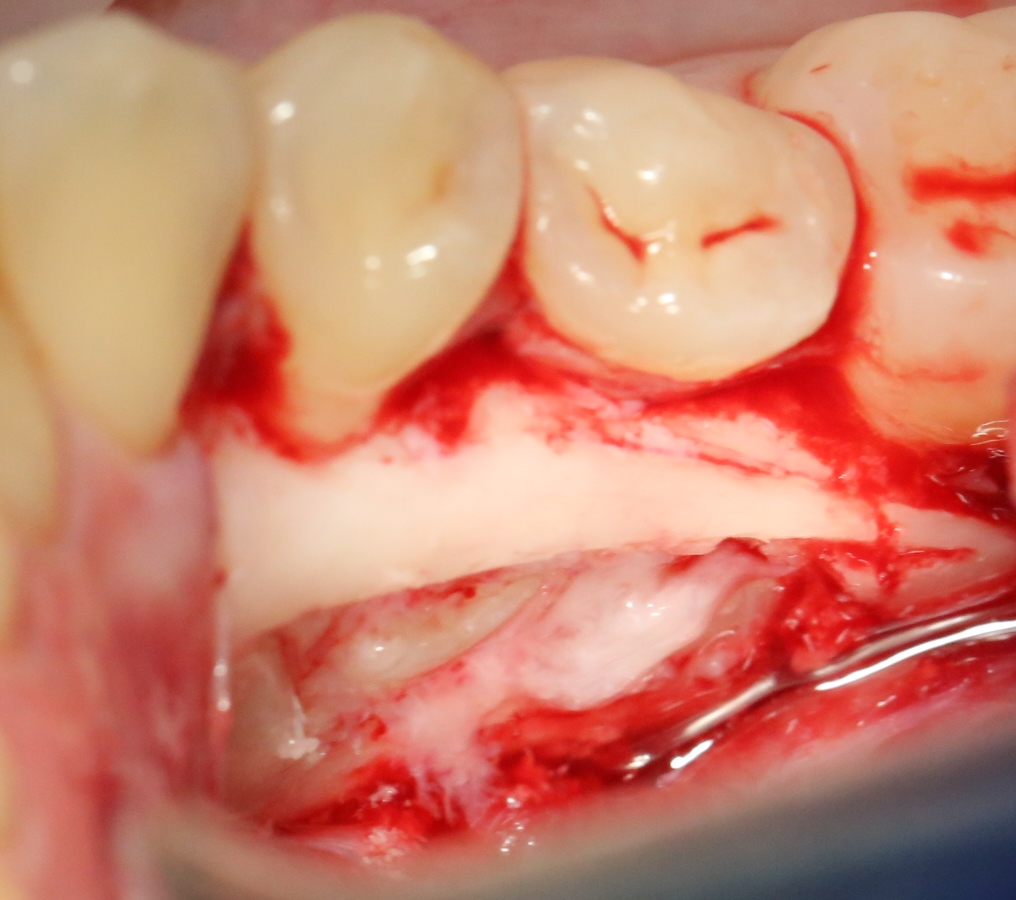

А вот их лунки:

Теоретически, лунки можно чем-нибудь заполнить. Только чем? И для чего?

Костная ткань сама регенерирует, если ей не мешать. Поэтому не стоит толкать в лунки какой-нибудь остеопластический материал, типа Cerabone или Bioss. Нет смысла.

В данном случае я использовал обычную коллагеновую губку — и то, только для того, чтобы «костная дверца», которую я выпилил в самом начале операции, не провалилась внутрь:

Теперь запиливаем «костную дверцу» на ее законное место:

И накладываем швы.